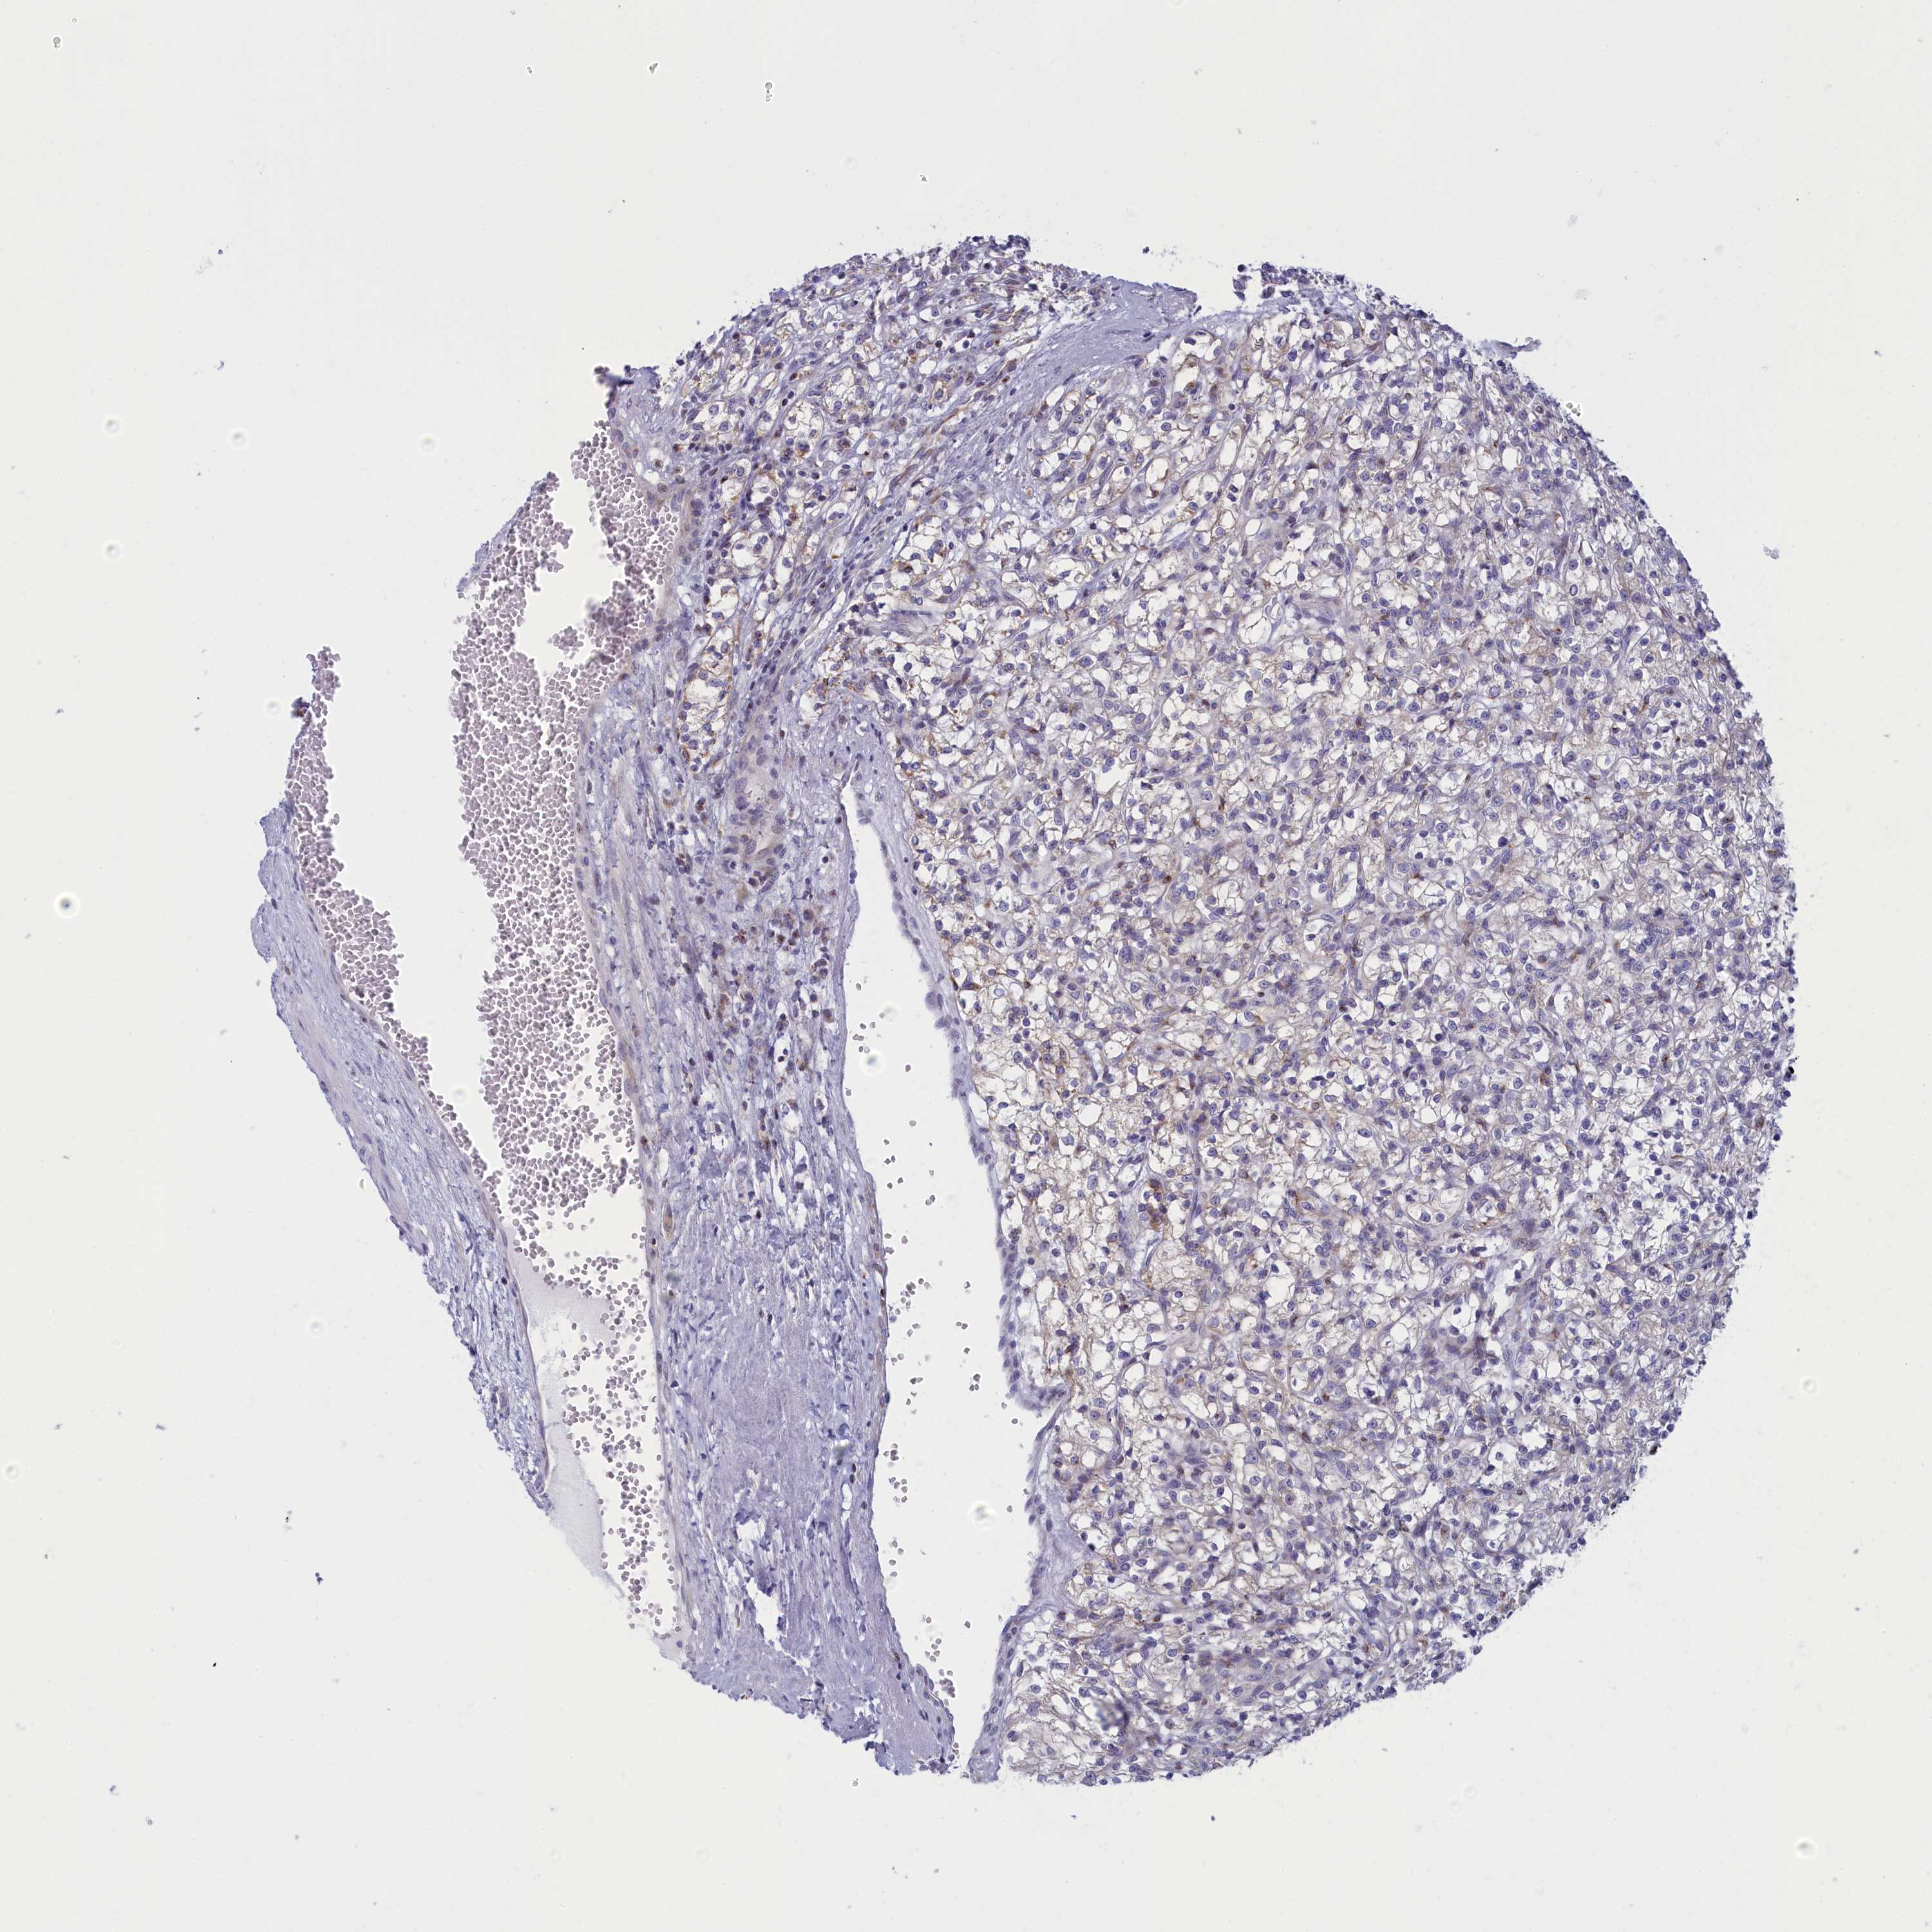

KIDNEY RENAL PAPILLARY CELL CARCINOMA (TCGA) - Interactive survival scatter ploti

The Survival Scatter plot shows the clinical status (i.e. dead or alive) for all individuals in the patient cohort, based on the same data that underlies the corresponding Kaplan-Meier plots. Patients that are alive at last time for follow-up are shown in blue and patients who have died during the study are shown in red.

The x-axis shows the expression levels (FPKM) of the investigated gene in the tumor tissue at the time of diagnosis. The y-axis shows the follow-up time after diagnosis (years). Both axes are complimented with kernel density curves demonstrating the data density over the axes. The top density plot shows the expression levels (FPKM) distribution among dead (red) and alive patients (blue). The right density plot shows the data density of the survived years of dead patients with high and low expression levels respectively, stratified using the cutoff indicated by the vertical dashed line through the Survival Scatter plot. This cutoff is automatically defined based on the FPKM cutoff that minimizes the p-score. The cutoff can be changed by dragging the vertical line or by entering a cutoff value in the square labeled "Current cut-off".

Under the Survival Scatter plot the p-score landscape (black curve; left axis) is shown together with dead median separation (red curve; right axis). Dead median separation is the difference in median mRNA expression between patients who have died with high and low expression, respectively. It is calculated as follows: median FPKM expression of dead patients with high expression - median FPKM expression of dead patients with low expression. This is intended to aid the user in visually exploring custom cutoffs and the associated p-scores and dead median separation.

Individual patient data is displayed and can be filtered by clicking on one or more of the category buttons on the top of the page. Categories describing expression level and patient information include: high, low, alive, dead, female, male and tumor stages. The scale of the x-axis can be toggled between linear and log-scale by clicking on the "x log" button. Mouse-over function shows TCGA ID, patient information and mRNA expression (FPKM) for each patient.

& Survival analysisi

Kaplan-Meier plots summarize results from analysis of correlation between mRNA expression level and patient survival. Patients were divided based on level of expression into one of the two groups "low" (under cut off) or "high" (over cut off). X-axis shows time for survival (years) and y-axis shows the probability of survival, where 1.0 corresponds to 100 percent.

NOL10 is potential prognostic, high expression is unfavorable in Kidney Renal Papillary Cell Carcinoma (TCGA)